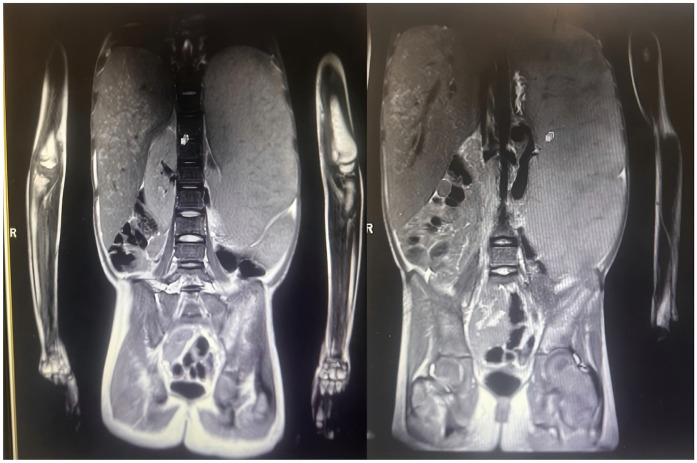

Results: A 12-year-old female patient from Kashgar, Xinjiang, China, presented with chronic anemia, hepatosplenomegaly, thrombocytopenia, recurrentepistaxis, and osseous pain. She was diagnosed with Gaucher disease type I through genetic testing and enzymatic examination. This case represents the first reported instance of this condition in the Xinjiang region. Notably, it exhibited unique clinical features, including the age of onset, severity of symptoms, and potential regional complications. Treatment with high-dose ambroxol and imiglucerase significantly alleviated the patient's symptoms, and continuous follow-up was conducted to assess long-term efficacy.